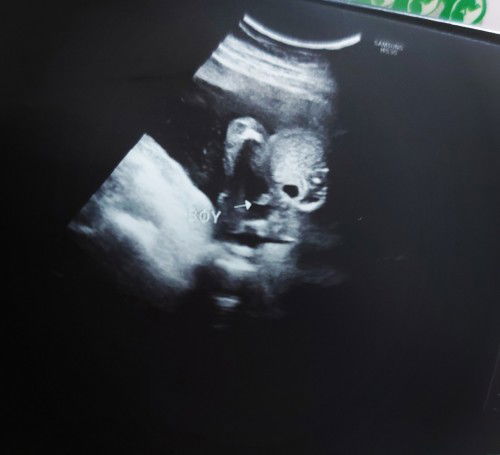

sakin nagpaultrasound aq 21 weeks dipa nakita taz breech pa sia.. hindi ba talaga nakikita ang gender kapag breech position ?

nakikita po mi kahit breech, kakapa Utz ko lang po breech pa sya 24weeks pero nakita naman po, hinahanapan lang po ng anggulo ng sonologist.

congrats mommy. sana ako din hihi 23weeks na kami ni baby , 80% boy daw di pa sure tlga nakadapa kasi

congrats po🥰 ilang weeks ka po nung nagpa ultra ka momsh at nalamang baby boy?

19weeks mommy ❤❤❤

congrats sis, ilang weeks k naun? #21weeks6days ako pero d mkita gender 😅